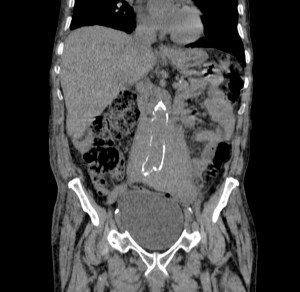

Paciente de 75 años de edad que acude a urgencias por cuadro de abdomen agudo. AP: Operado de hernia inguinal hace 48 horas. Alteración de las constantes vitales, se sospecha perforación por lo cual se demanda TAC de abdomen.

Veamos los hallazgos en una TAC con y sin contraste:

Decimos masa en este caso, aunque se podría pensar que es un sangrado de aneurisma. ¿Por qué no es esta última opción? Observar en primer lugar las paredes de la aorta delimitada por calcio, es decir, sus paredes están calcificadas. Para que pudiésemos hablar de aneurisma, nuestra masa debería tener el calcio en su perifería, Signo del calcio tangencial, y esto no ocurre. La aorta está calcificada y no está sangrando, lo cual se ve reforzado por el hecho de que la masa rodea de una manera uniforme y armoniosa la aorta; un sangrado no sería tan regular, no rodearía de una manera tan perfecta la arteria y además habría predominio de sangrado hacia algún lado de nuestra aorta. Solución: Estamos ante un linfoma.